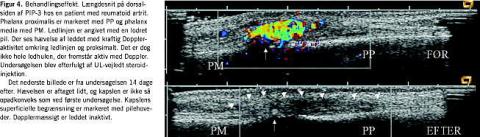

Hos patienter med kliniske tegn på inflammation kunne farve-Doppler anvendes på de overfladenære led og seneskeder. Der kunne således påvises Doppler-aktivitet i alle de små led på hænder og fødder (Figur 1 ), i sternoklavikulærled, albueled, ankelled og knæled. I modsætning hertil var Doppler-aktivitet kun undtagelsesvist til stede i dybereliggende led som f.eks. skulderled og hofteled trods klinisk erkendelig ledsygdom, typisk artrit. Hos raske kontrolpersoner kunne der påvises Doppler-aktivitet i visse led. Således var det et næsten konstant fund ved undersøgelse af leddet mellem caput radii og capitulum humeri, mens det sjældnere blev observeret i håndled og ikke i fingerled. Der kunne ligeledes påvises Doppler-aktivitet både i og omkring symptomgivende akillessener og ligamenta patellae. Seneskeder med klinisk tenosynovit med og uden gråtone-UL-forandringer havde overvejende Doppler-aktivitet langs senen (Figur 2 ). Doppler-funktionen kunne ligeledes supplere gråtonebilledet ved differentiering af en meget ekkofattig synovialis fra fri væske i led og omkring sener ved påvisning af kar i den ekkofatt ige del af vævet (Figur 3 ).

Vi fandt desuden, at der i de fleste tilfælde af vellykket systemisk eller lokal behandling af inflammatoriske tilstande i bevægeapparatet sås et fald i antallet af farvede pixler i målområdet (Figur 4 ).